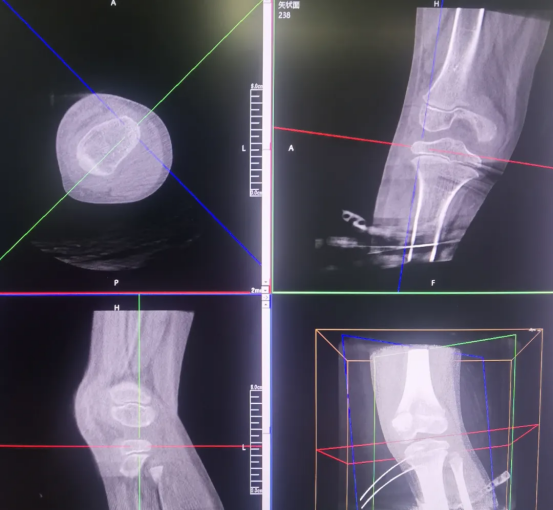

Screw placement is a critical step in the surgery. It requires accurate placement in specific epiphyseal regions of the femur and tibia, which not only achieves the growth inhibition effect but also avoids damaging healthy epiphyses, blood vessels, or nerves, imposing demanding exceptional surgical accuracy. When locating the target sites (such as the femur and tibia) , surgeons can clearly identify the position of the epiphyseal plate using Perlove Medical’s 3D C-arm. This helps them define the safe zones for drilling and screw insertion, establish an optimal relative relationship between the screws, epiphyses, and bone axes, and eliminate risks like screw deviation or bone penetration.

Perlove Medical’s 3D C-arm performs postoperative scans to verify screw placement from multiple dimensions: the relationship between the screws and the epiphyseal line

, any loosening or displacement and whether the femoral and tibial mechanical axes are approaching balance. If any subtle issues are detected, timely adjustments can be made to ensure optimal screw fixation. This postoperative 3D verification eliminates the observation blind spots in 2D imaging and serves as the final safeguard for surgical outcomes and long-term skeletal health.